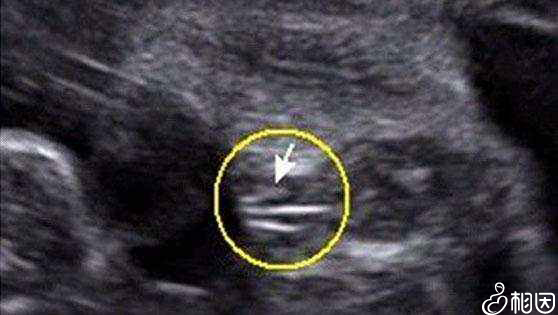

民间一直有孕囊看男女的说法,说可以通过B超检查报告上的孕囊形状,来判断胎儿性别。不过通过孕囊看男女,必须满足以下两个条件:

因为孕囊都是圆柱形的,每个B超师截取的时候截取得方位都会不一样。有的是横截取面,有的是竖截取面。所以只看图片是长的还是圆的是不能判断男女的。

通过孕囊数据看男女

打个比方,比如:40*20mm的孕囊,这样是根本没有办法判断的,表面看起来两个数据相差一倍,应该是男孩。但是错了,因为没有第三个数据。如果是40*40*20,那就肯定是男孩了。

但如果b超师截取横截面,孕囊就成了40*40的两个数据了,看上去就是圆的,结果造成了孕囊是圆的,但是生的是儿子。所以数据一定要三个,如果孕囊成等差比:40*30*20这样的就是女孩。